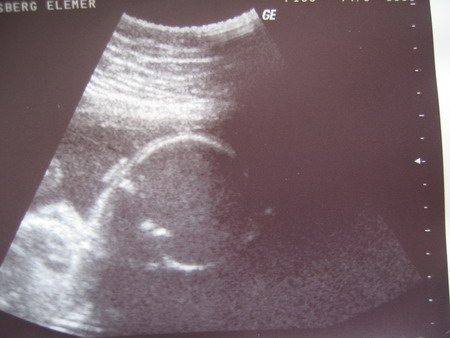

Kiváncsi vagyok, mit mond majd a dokid! De nem lesz ám semmi baj a szülésnél, jó kezekben leszel, meglátod!